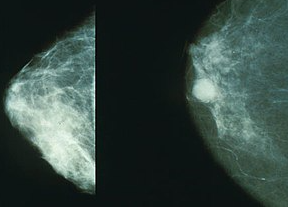

우리가 유방암에 대해서 모르고 있는 두 가지가 있다. 하나는 유방암의 원인이고, 다른 하나는 유방암의 치료법이다.

-낸시 브링커(유방암특별위원회 의장)-

아무도 예방법을 모르고, 유방암이 증가하는 원인은 수십 년 동안 밝혀지지 않았다.

-뉴욕타임스-

빈부격차와 관계없이 도사와 농촌의 차이에 관계없이 유방암은 미전역에 걸쳐 증가하고 있다. 하지만, 증가원인은 밝혀진 바 없다.

-사이언스 뉴스-

솔직히 유방암의 원인을 모른다. 더욱이 유방암의 원인을 규명할 단서조차 가지고 있지 않다.

-수잔러브 박사(하버드 의대 교수)-

우리가 그 원인을 알았더라면 예방법도 찾아낼 수 있을 것이다. 그러나 우리는 아직도 알지 못한다.

-자넷 오슈아 박사(미시간주립대 유방암 연구원)-